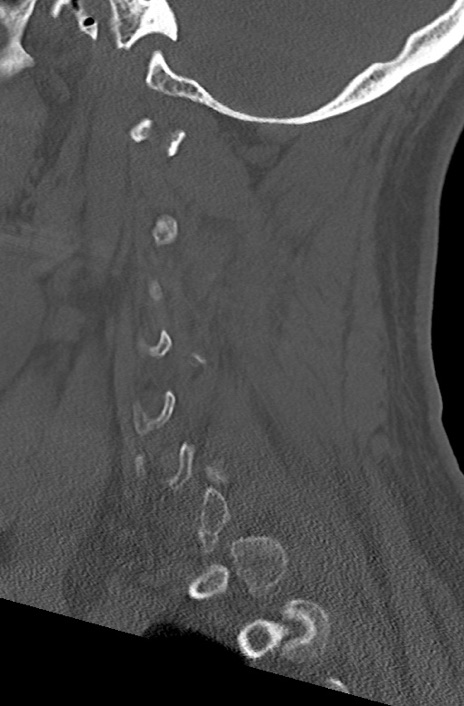

頚椎CT

冠状断像